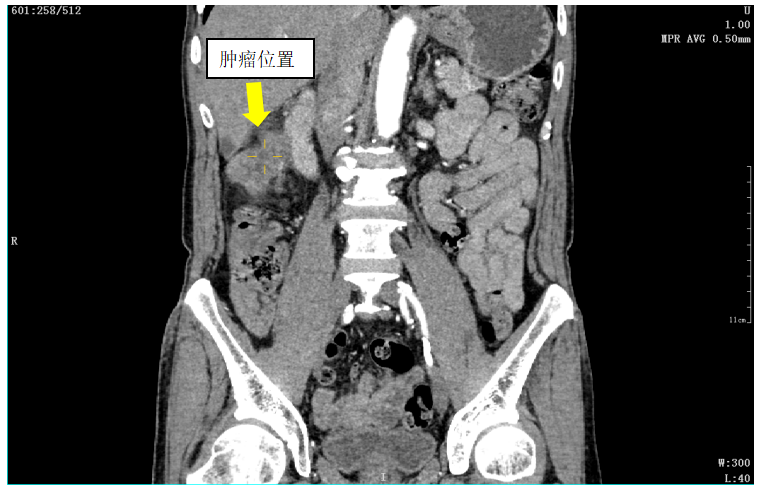

为了进一步查清原因,温伯被收入普外科住院部,随后的腹部CT检查显示,温伯属于乙状结肠、降结肠交界区肿瘤,并突破浆膜,周围肠系膜多枚淋巴结。

▲温伯肿瘤位置